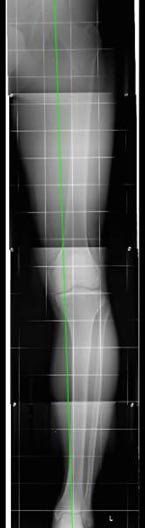

In den letzten 15 Jahren ist das Konzept der so genannten Umstellungsosteotomie entscheidend weiterentwickelt worden, sodass dieses Knorpeloperations-Verfahren seinen Schrecken verloren hat. Das Vorgehen ist in diesem Fall folgendermaßen: Es wird zunächst eine genaue Diagnostik mittels Röntgen vorgenommen, diese erfolgt mit Hilfe einer so genannten Achsaufnahme des gesamten Beines im Stand. Anhand dieser Aufnahme wird die Fehlstellung sowohl innen oder außen am Kniegelenk genau ausgemessen. Dann wird ausgemessen, wie durch ein kleines aufbiegendes Verfahren am Schienbeinkopf (häufigste Vorgehensweise) oder durch eine Einkerbung des Oberschenkelknochens (selteneres Verfahren) die Achse entsprechend der Stelle, an der die Verschiebung am Bein vorhanden ist, bei der Knorpeloperation wieder korrigiert werden kann. Durch neu entwickelte Instrumente handelt es sich dabei nicht mehr um ein Verfahren, wo der Knochen zum Beispiel am Schienbein komplett durchgeschnitten werden muss, sondern es erfolgt mehr oder minder eine Einkerbung des Knochens und der Knochen wird etwas aufgebogen. Damit der Knochen sich nicht sofort wieder verschließt, wird eine kleine Metallplatte angebracht, die den Knochen offen hält.